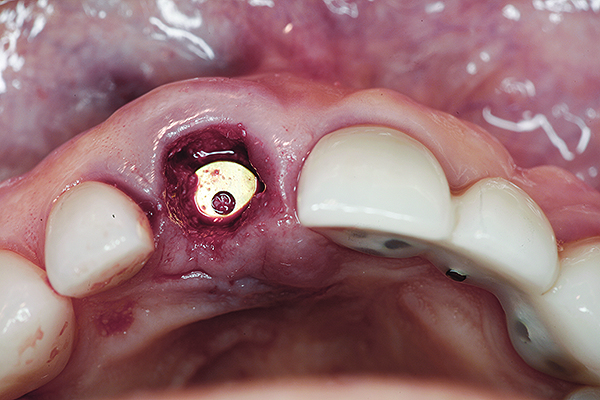

A 63-year-old female patient presented with mobility of her right maxillary incisor, tooth No. 8, secondary to endodontic therapy (Figure 1). Her medical and dental histories were non-contributory. Clinical and radiographic evaluations revealed an 8-mm probing depth on the palatal aspect. The tooth was deemed to be fractured (Figure 2). The treatment plan accepted by the patient was for extraction, immediate implant placement, and immediate provisional restoration, if possible.

Fig 1. Preoperative clinical photograph of fractured maxillary right central incisor (tooth No. 8).

Figure 1

Fig 16. Try-in of the definitive titanium-nitride–coated abutment.

Figure 16